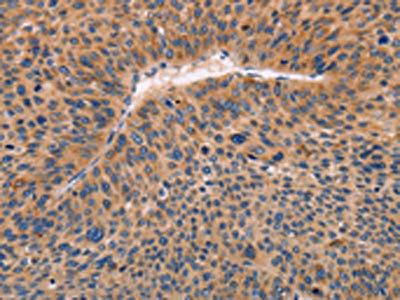

The image on the left is immunohistochemistry of paraffin-embedded Human liver cancer tissue using CSB-PA023292(ADAMDEC1 Antibody) at dilution 1/20, on the right is treated with fusion protein. (Original magnification: ×200)